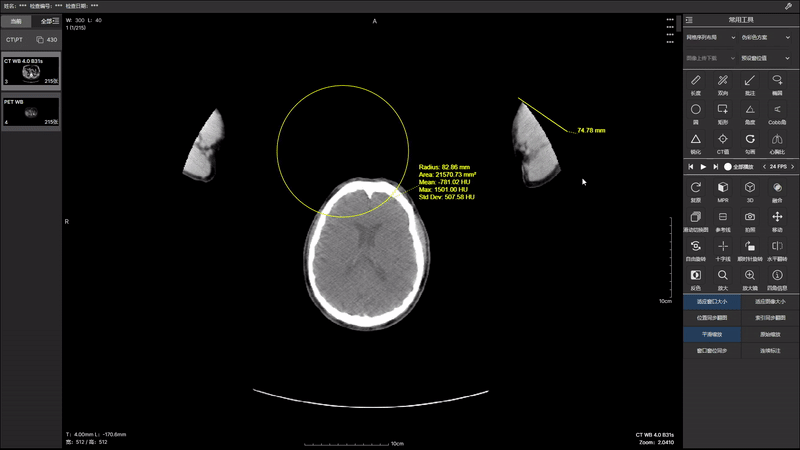

通过先进的算法和技术,我们在 2.0 版本中实现了 PT(正电子发射断层扫描)和 CT(计算机断层扫描)图像的无缝融合。这项突破性技术将为医生提供更全面、 更立体的患者图像,并且2.0 版本的图像融合带来了更高的分辨率和更丰富的图像细节。医生能够更准确地识别病变、评估组织状态,提高诊断的灵敏性和特异性, 为患者制定个性化的治疗方案提供更强有力的支持。医生可以更轻松地导航和比对 PT 和 CT 图像,提高工作效率。智能化的界面设计使操作更直观。 升级你的医学影像诊断体验,与 PT CT 图像融合 2.0 版本一同开启医学影像新时代。提升准确性,优化工作流程,为患者提供更全面的医疗服务。